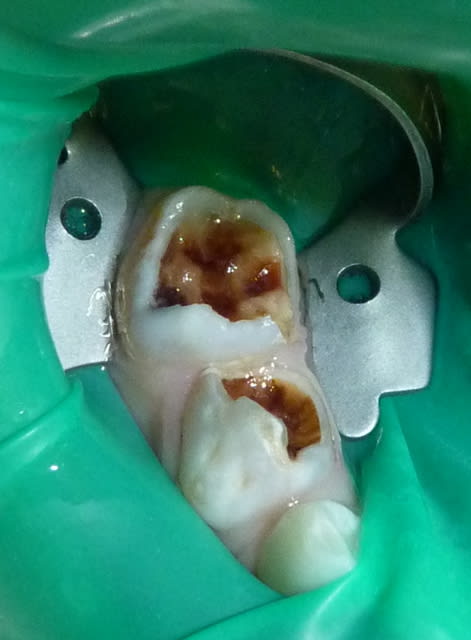

05/07/11 : secteur IV.

85 n'a plus de parois vestibulaire/linguale. 84 n'a plus de paroi linguale.

J'utilise un composite plutôt qu'un CVI pour une meilleure adhésion et résistance mécanique sur ces dents très délabrées. J'essaie de recréer des bombés sur les moignons.

Semaine prochaine : les antérieures.

Dans le cas ci-dessous, la 1ère photo est prise après début d’éviction carieuse : sur la 4, on voit déjà la pulpe par transparence. Les tubuli dentinaires d'une dent temporaire sont beaucoup plus larges et nombreux que sur une dent permanente. Ainsi, une carie dentinaire infecte très rapidement la pulpe camérale. Faire une restauration sans pulpotomie dans ce cas aurait probablement abouti à une nécrose à moyen terme.

P1010955 lkrpua - Eugenol

P1010959 qtf3fy - Eugenol

P1010962 ddzmfk - Eugenol

P1010966 tt9pyf - Eugenol

P1010974 bokjpr - Eugenol